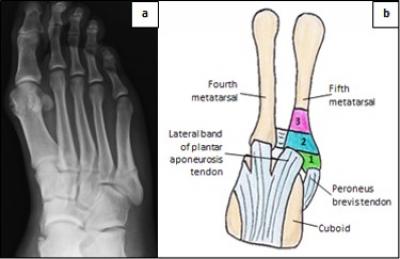

Figure 1: a) Radiograph of fifth metatarsal fracture (Tan et al. 2016). b) Diagram of fifth metatarsal showing related tendons and fractures’ zones